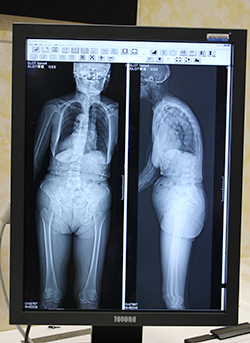

また,オプション搭載できる“SLOT Advance”は,歪みの少ない長尺画像を取得できるアプリケーションで,全脊椎や全下肢の精度の高い計測が可能になる。今回,画像処理の大幅な高速化が図られ,スキャン終了後約7秒で,つなぎ合わせがすんだ最終画像がモニタに表示される。長尺撮影で立位と臥位の両方を撮影する施設では,2体位目の撮影のためにベッドを動かしている間に1体位目の画像再構成が終わり,同じポジションのまますぐに撮影ができるので,非常に高いスループットを実現できる。

画像再構成の高速化が図られた

SLOT Advance